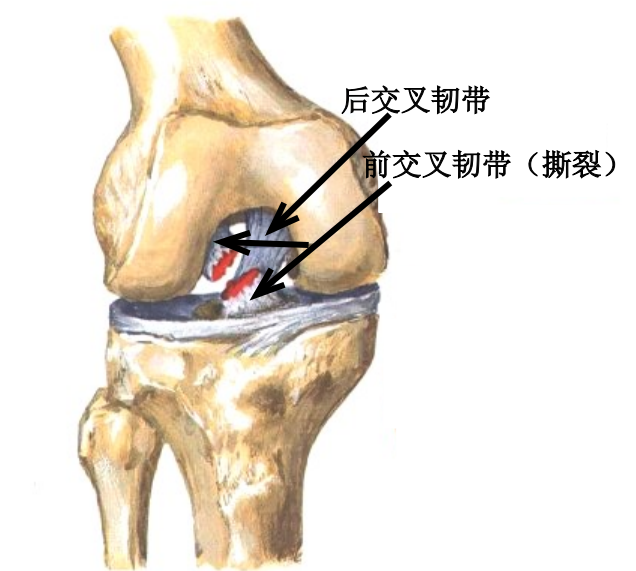

ACL 解剖

前交叉韧带起自股骨外侧髁的内侧面,斜向前下方,止于胫骨髁间隆起的前部。ACL 分为前内束(AM)和后外束(PL)。当屈膝 30° ~ 40° 时,前交叉韧带的张力最小。